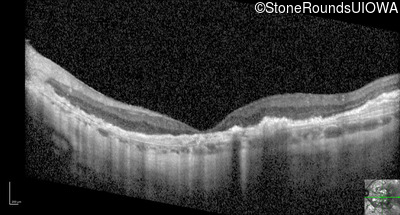

Optical Coherence Tomography - Right - 20/200 +2

Exemplar / OCT Stack